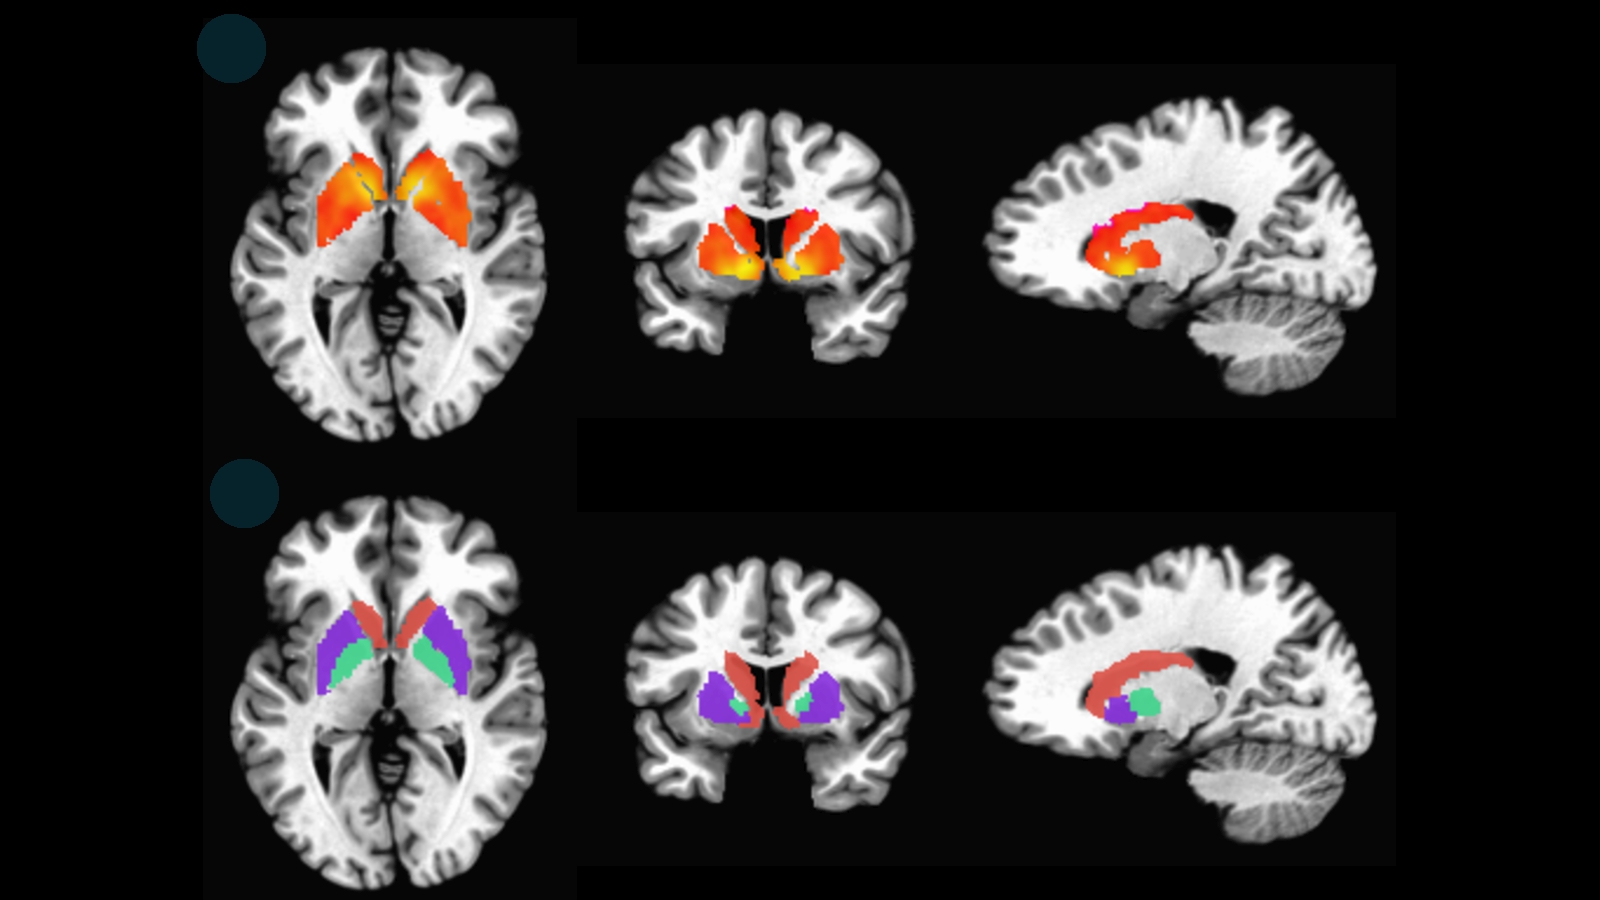

Η μελέτη βασίστηκε στην τεχνική της λειτουργικής μαγνητικής τομογραφίας, ή fMRI, μια παραλλαγή της μαγνητικής τομογραφίας που παρακολουθεί την εγκεφαλική δραστηριότητα μετρώντας τη ροή οξυγόνου στον εγκέφαλο.

Οι ερευνητές εστίασαν στο «δίκτυο βασικής κατάστασης» (DMN, Default Mode Network), ένα δίκτυο του εγκεφάλου που πλήττεται πρώτο από την Αλτσχάιμερ. Το DMN είναι υπεύθυνο για τις σκέψεις που παράγονται όταν δεν κάνουμε τίποτα και επιπλέον συνδέει διαφορετικές περιοχές του εγκεφάλου που αναλαμβάνουν συγκεκριμένες γνωστικές λειτουργίες.